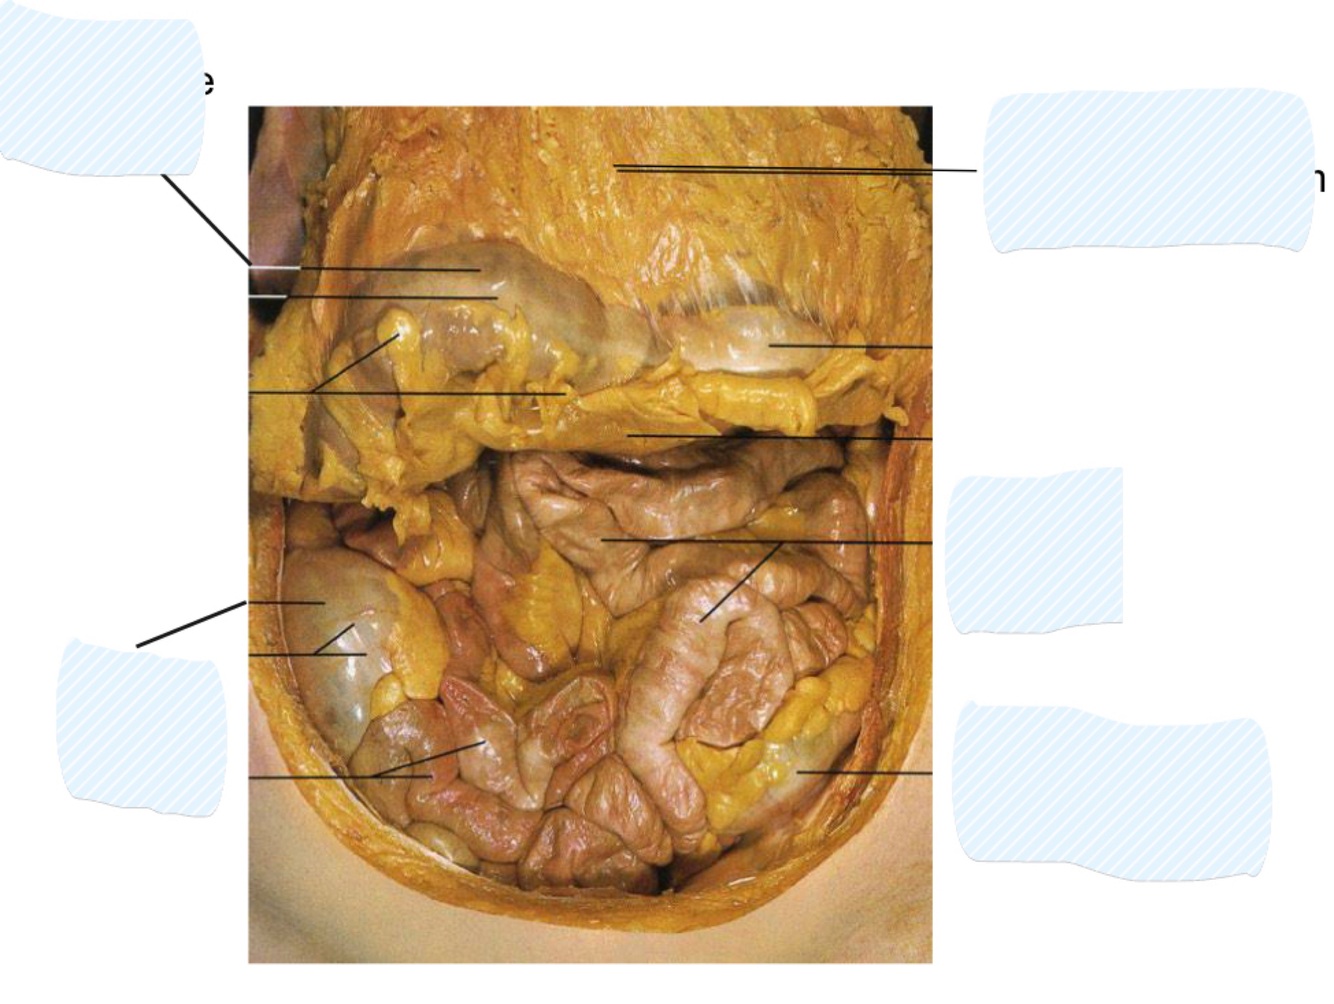

What dies the large intestine consist of?

Consists of cecum,

colon, and rectum

Colon divided into:

• Ascending

• Transverse

• Ascending • Transverse • Descending • Sigmoid

• Ascending and

descending colon

are retroperitoneal

• Transverse and

sigmoid colon are

intraperitoneal